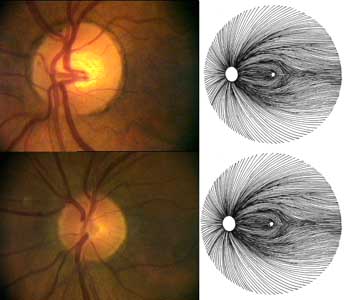

Zatímco terč zrakového nervu mezi lidmi značně kolísá co do velikosti i tvaru, vrstva nervových vláken, jak popisuje Airaksinen, je uspořádána zcela shodně u každého člověka.

Ze změn terče lze pouze usuzovat na změny zorného pole, zatímco defekty ve vrstvě nervových vláken odpovídají změnám zorného pole s velkou přesností, dokonce jim často i předcházejí.